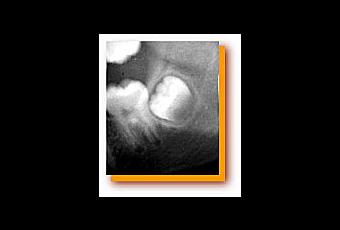

Généralement demandée par l'orthodontiste, au plus tard en fin de traitement, l'extraction des dents de sagesse est parfois prescrite dès l'âge de douze ans pour retirer les germes

en formation dans les mâchoires et ce alors qu'on ne sait même pas s'il y aura des problèmes d'éruption. On parle alors de germectomie qui

présente de nombreux effets secondaires.